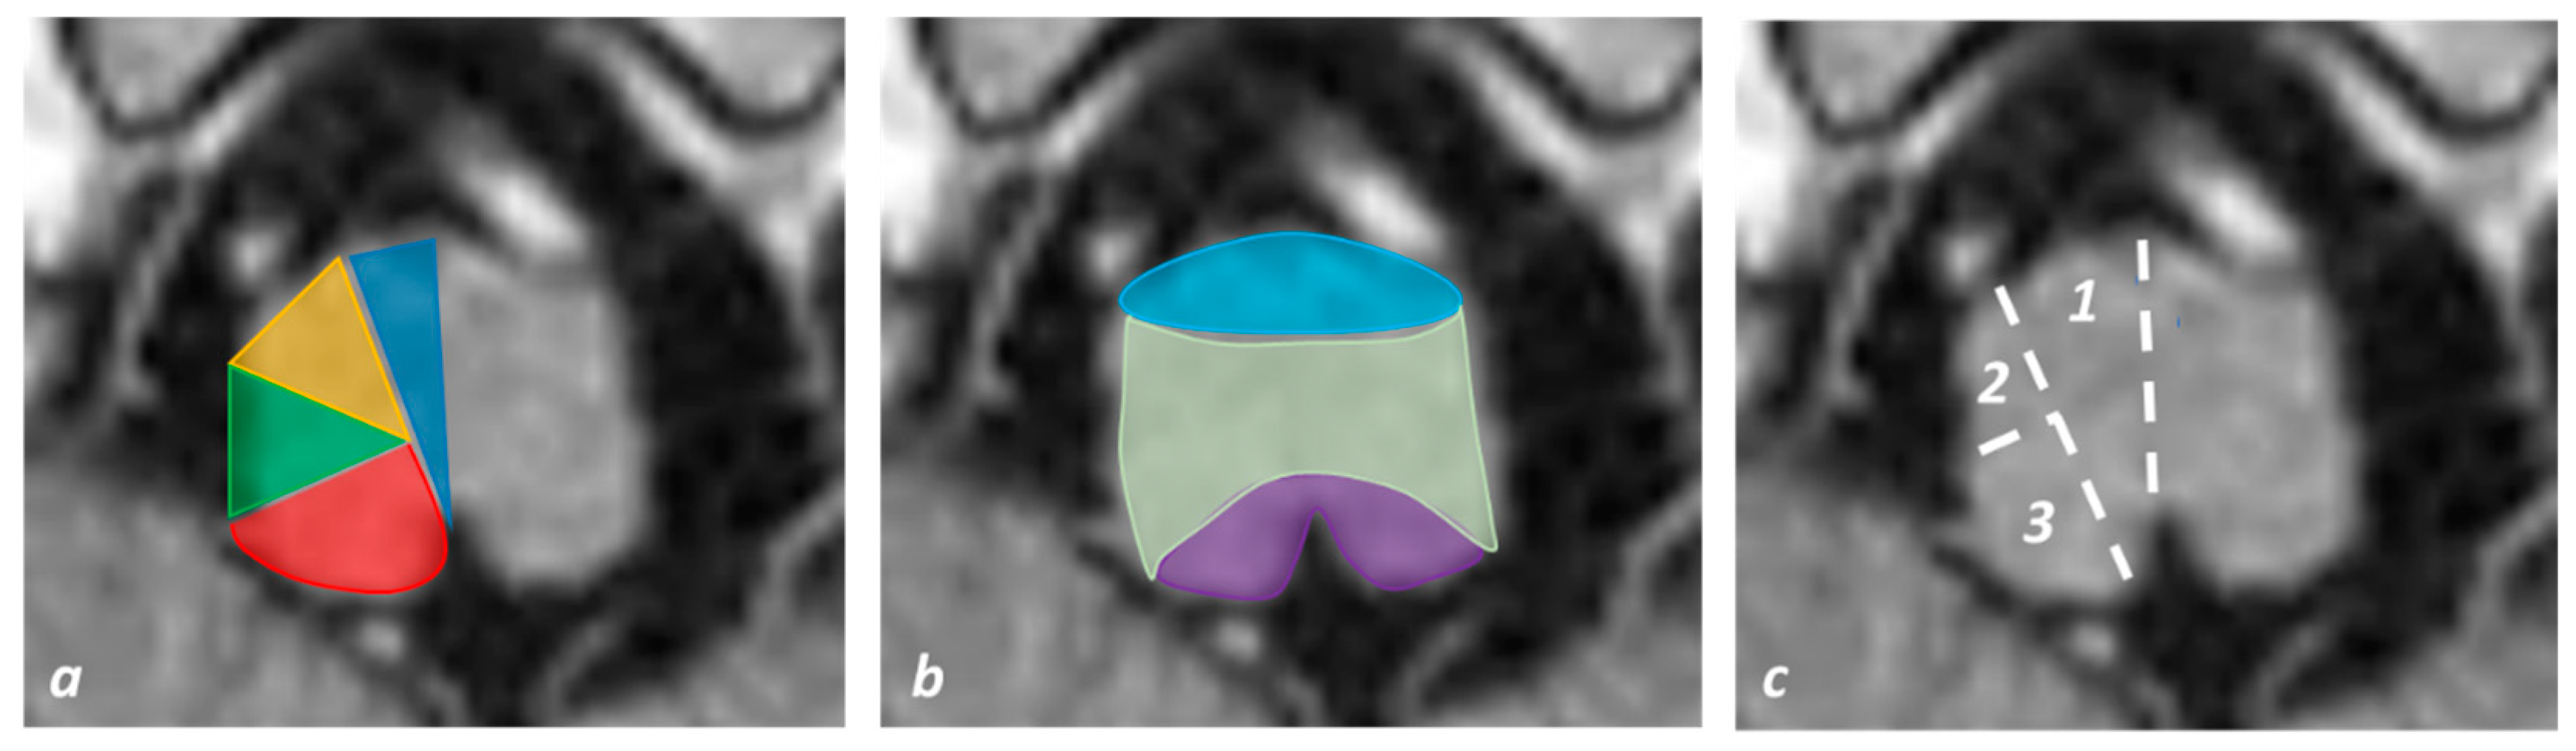

- Vlašković, T.; Brkić, B.G.; Stević, Z.; Vukićević, M.; Đurović, O.; Kostić, D.; Stanisavljević, N.; Marinković, I.; Kapor, S.; Marinković, S. Anatomic and MRI Bases for Pontine Infarctions with Patients Presentation. J. Stroke Cerebrovasc. Dis. 2022, 31, 106613. [Google Scholar] [CrossRef]

- Kataoka, S.; Hori, A.; Shirakawa, T.; Hirose, G. Paramedian pontine infarction: Neurological/topographical correlation. Stroke 1997, 28, 809–815. [Google Scholar] [CrossRef]

- Venkatesan, P.; Balakrishnan, R.; Ramadoss, K.; Iyer, R.S. Heart appearance sign in pontine stroke: A result of bilateral infarction due to small vessel disease. Neurol. India 2014, 62, 115–116. [Google Scholar] [CrossRef]

- Sen, D.; Arora, V.; Adlakha, S.; Gulati, Y.S.; Doppaladudi, A.; Tiwary, S. The “Heart Appearance” Sign in Bilateral Pontine Infarction. J. Stroke Cerebrovasc. Dis. 2015, 24, e21–e24. [Google Scholar] [CrossRef]

- Zhou, C.; Xu, Z.; Huang, B.; He, Y.; Zhu, Y.; Zhao, Y.; Wang, P. Caudal paramedian midbrain infarction: A clinical study of imaging, clinical features and stroke mechanisms. Acta Neurol. Belg. 2019, 121, 443–450. [Google Scholar] [CrossRef]

- Zhou, C.; He, Y.; Chao, Z.; Zhu, Y.; Wang, P.; Gao, X. The “heart appearance” sign on MRI of Wernekink’s commissure syndrome caused by bilateral caudal paramedian midbrain infarction. Neurol. Sci. 2017, 39, 587–589. [Google Scholar] [CrossRef] [PubMed]